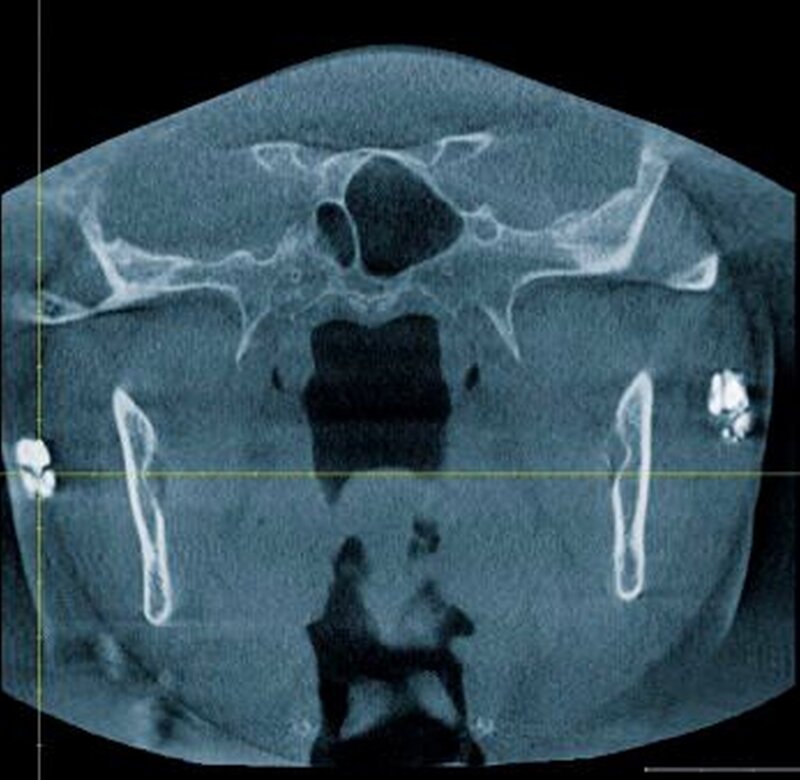

Dabei imponierten neben der periradikulären Aufhellung in regio 045 mehrere unregelmäßig angeordnete, wolkige, begrenzte Strukturen im Bereich des rechten und linken aufsteigenden Unterkieferastes. Außerdem waren unterhalb des rechten Ramus mandibulae in Höhe des Os hyoideum und im Bereich des linken Ligamentum stylomastoideum röntgenopake Strukturen sichtbar. Anamnestisch berichtete die Patientin von einer abgelaufenen Tuberkulose der Speicheldrüsen im Kindesalter, deren Spätfolgen im Sinne von Kalzifizierungen anhand der radiologischen Befunde palpiert werden konnten.

Zur genauen räumlichen Zuordnung der Verschattungen unterhalb der Incisurae semilunares wurde eine dentale digitale volumentomografische Untersuchung durchgeführt (Abbildungen 2 bis 4).